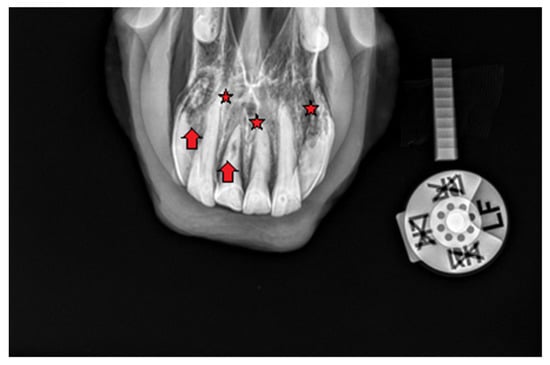

2.1.1. Case 1